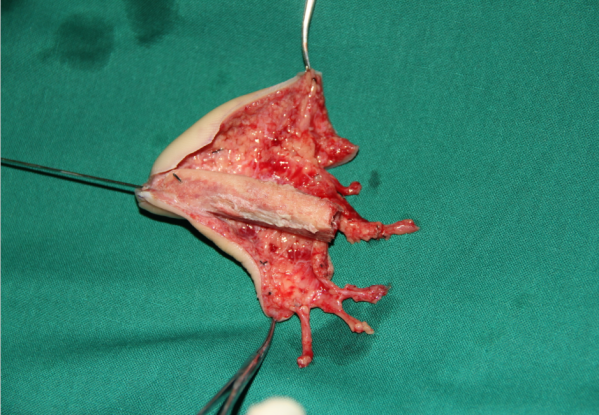

玉米机伤右足复合组织缺损,腓骨皮瓣修复,术后12天,伤口愈合良好,今日出院清创后

跖趾关节成形